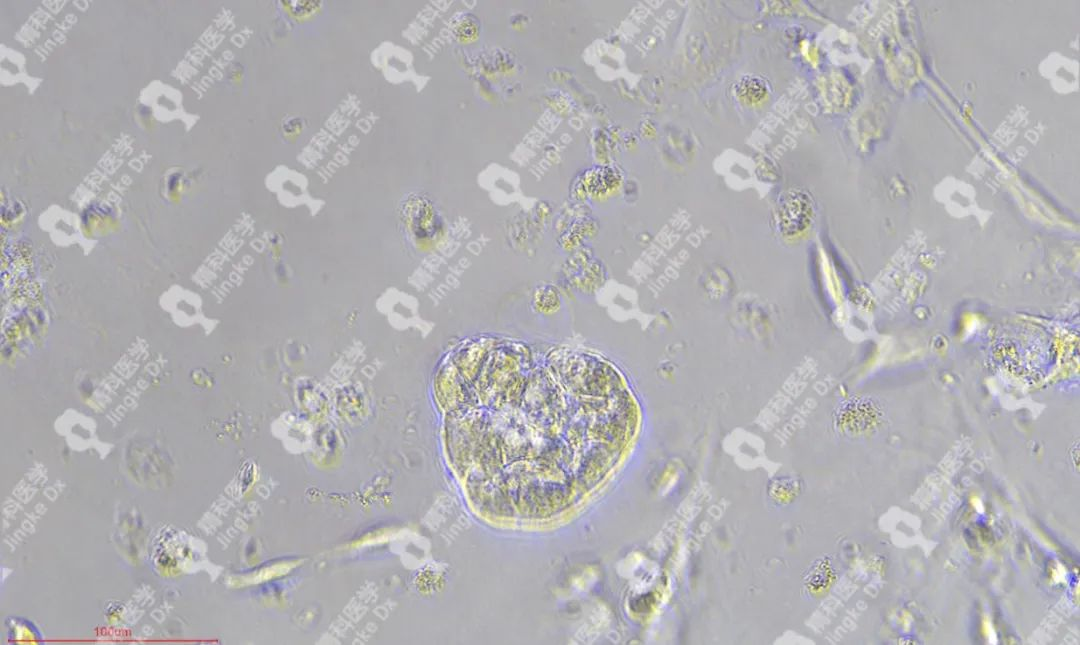

PIC.01

精科卵巢癌類器官圖像